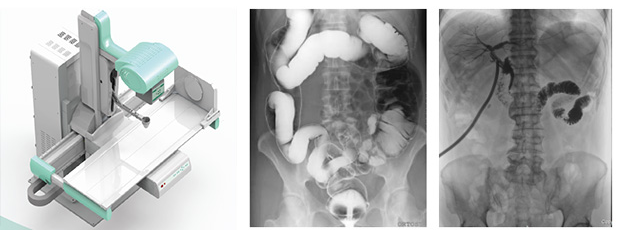

随着现代医疗技术快速发展,传统的X射线技术实现数字化,出现了多功能DR。多功能DR采用数字影像平板探测器取代传统胶片,直接捕获X线影像,并转化为高清晰数字图像,对比传统的间接影像设备,多功能DR可以直接将X射线转化成图像,成像更清晰,放射剂量更小。

多功能DR大大提高了普通放射设备准确诊断的能力,为临床创造了价值,它可以进行全身各部位的拍片、透视和点片摄影。接下来小编给大家介绍一下这三种模式的区别。

多功能DR